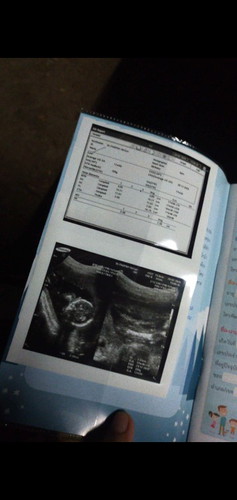

สวัสดีครับทุกคนหลังจากผมอยู่กับพ่อกับแม่มา4เดือนฟ่า เมื่อวานผมไปหาหมอครั้งแรกมาแล้วน้ะครับ ร่างกายสมบูรณ์ หมอบอกผมก็ตัวใหญ่อยู่น้ะ แม่ผมไม่ค่อยได้บำรุง ผมจะมาอับเดตรูปผมบ่อยๆน้ะครับ #ปลายเดือนธันวา หลังจากนี้แม่ผมต้องแบกท้ิงที่มีผมไปฝึกงานและก็เรียนไปด้วย ขอกำลังใจให้แม่ผมด้วยน้ะครับ💕